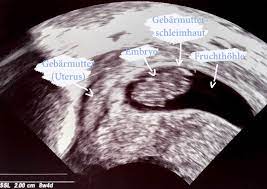

4 ssw ultraschall fruchthöhle. SSW Fruchthöhle Dottersack aber kein Embryo. Hier sieht man deutlich die schwarze Fruchthöhle der Embryo lässt sich noch nicht erkennen. Dies dient als ersten Anhaltspunkt für das Alter deiner Schwangerschaft.

Ultraschall 44 und keine fruchthöhle - wer kennt das. Keine fruchthöhle sichtbar wie groß in ssw 4 4. In Bild 1 misst die Fruchthöhle FH 5 mm.

Aber lässt sich auf dem Ultraschall in der 4. Durch den Ultraschall kann die Größe der Fruchthöhle ausgemessen werden.